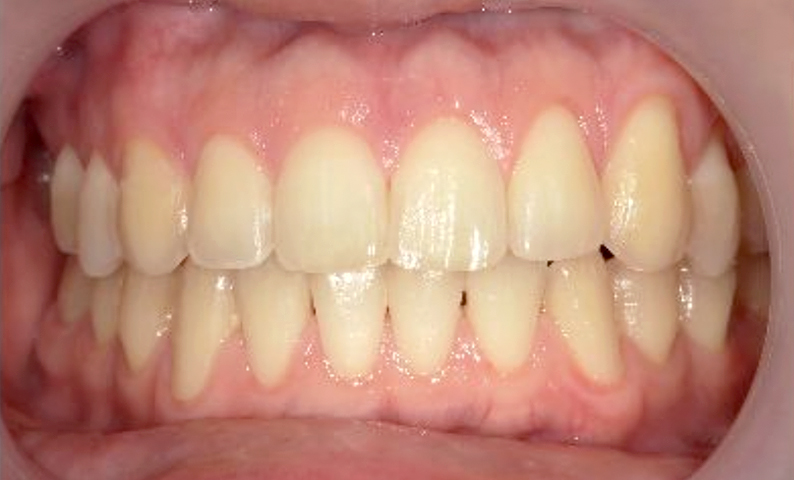

症例_001 前歯「すきっ歯」症例

治療期間:9ヶ月金額:51万円+税20代女性すきっ歯

| Before | After |

|---|---|

|